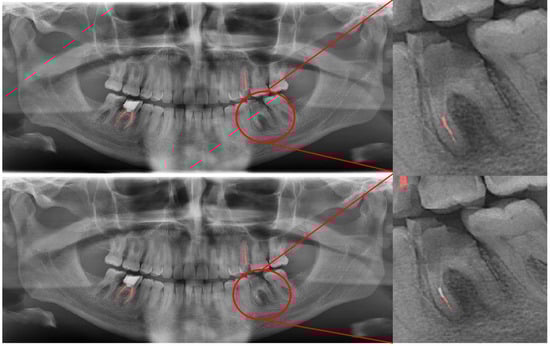

Figure 8.

Erroneous automatic segmentation at the maxillary left third molar due to the superimposition between the maxillary sinus floor and root apices of the tooth. Manual segmentation (upper image) and automatic segmentation (lower image) can be seen above.

In Figure 8, a more successful automatic segmentation is observed at the maxillary right third molar than the maxillary left third molar, and a missing segmented area in the form of a notch is observed. As most of the upper third molars were superimposed on the floor of the maxillary sinus and zygomatic process of the maxilla, erroneous segmentations were inevitable. In Figure 9, an erroneous automatic segmentation at the mandibular left second molar due to the superimposition between the mandibular left first and mandibular left second premolars can be seen.